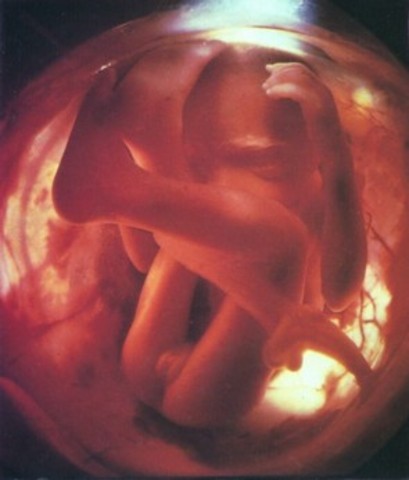

• 7 month

This fetus is now about 15 inches long and weighs between 1 and a half - 2 pounds. It can cry weakly and can suck its thumb. The fetus can make a variety of reflex movements: startle, grasp, and swim movements. The cerebral hemispheres cover almost the entire brain.